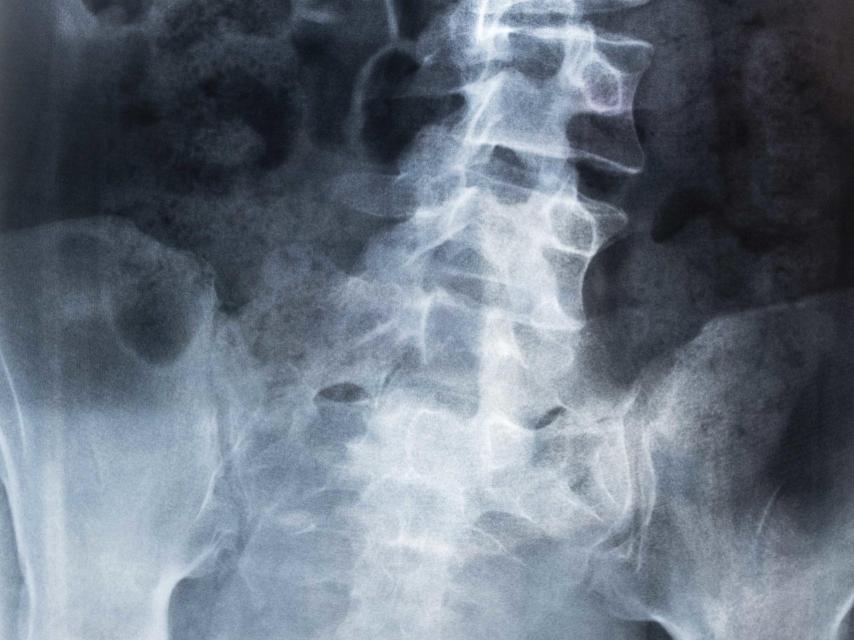

Tras llevar a Alba al médico, con seis años le diagnosticaron una escoliosis de 33 grados, una desviación lateral severa de la columna vertebral. Con el paso del tiempo, su cuerpo se fue deformando. Desde hace año y medio, su vida ha transcurrido sobre una cama. El pasado 27 de febrero cambió el colchón de su casa por uno de una habitación en la segunda planta del hospital de Jerez de la Frontera (Cádiz), donde aún hoy sigue ingresada.

Alba comenzó a padecer dolores a los 11 años, cuando desarrolló. Se quejaba a su madre de que le dolía la zona derecha de la ingle. Tras acudir al hospital, un médico le dijo que tenía rotada la cadera y que había que intervenir.

Fue entonces cuando a Alba la derivaron a los especialistas de columna. Un día antes de jubilarse, un galeno del hospital Virgen del Rocío de Sevilla le dijo a Carolina que, bajo su criterio médico, “el problema de Alba era de columna más que de cadera”. Al poco de cumplir los 16 años, Alba entró por segunda vez en quirófano. Fue en el hospital de referencia de la provincia de Cádiz, el Puerta del Mar.

A Alba le limaron la protusión lumbar (no alcanza a una hernia) que tenía en la parte baja de la espalda. También le abrieron los canales de los nervios de la columna. Pero la operación no resultó positiva para la adolescente. A los pocos días “rabiaba de dolor”, cuenta su madre. En las semanas y meses posteriores le realizaron varias infiltraciones con corticoides y anestésicos para mitigarlo. Hasta que llegó el día que dejó de moverse y quedó postrada en una cama.

“En el hospital de Cádiz se niegan a operar de nuevo a mi hija -explica Carolina Pacheco-. El médico especialista dice que Alba padece un escoliosis congénita y que no tiene solución. El SAS (Servicio Andaluz de Salud) está desahuciando a una chiquilla de 18 años. La condena a vivir postrada en una cama el resto de sus días. Pero sé que no la operan porque saben que metieron la pata en la anterior intervención. Estos dolores que padece mi hija ahora son inhumanos. Son calambrazos muy bruscos que le llegan hasta la punta de los dedos de los pies”.